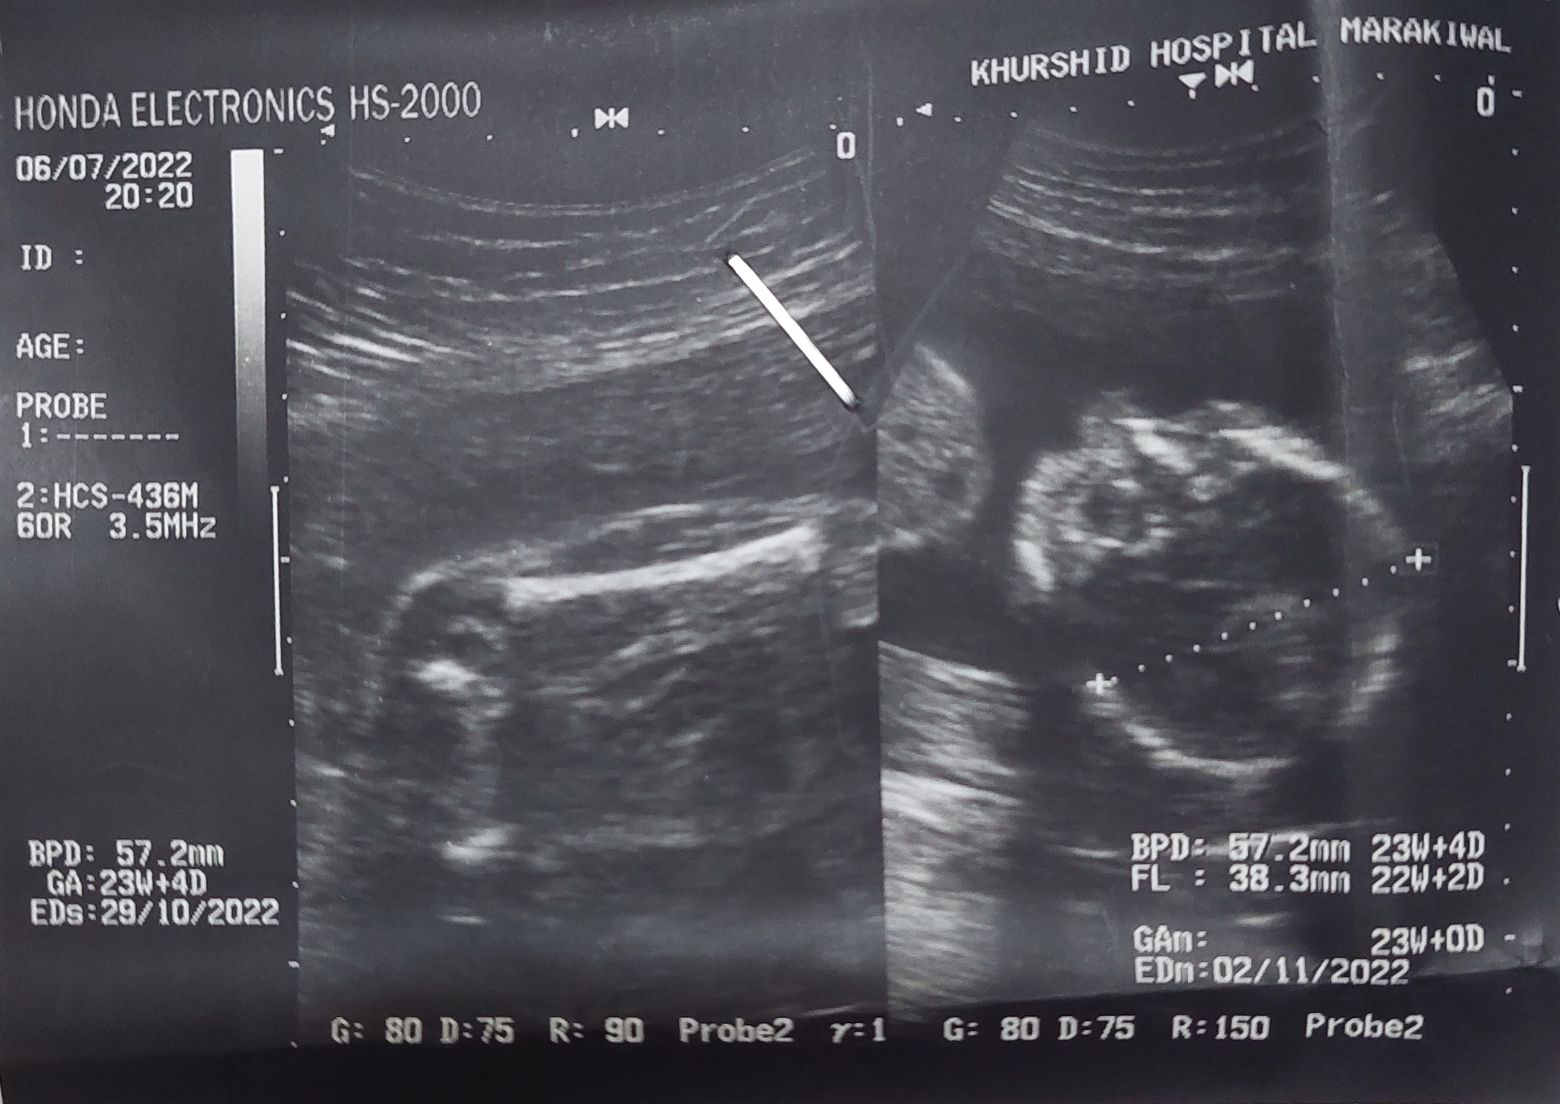

Hey dr I am 22 weeks pregnant I want to know the gender of my baby because its my first child What when ever i asked my dr she said i am not clear about this right now Can i go for anatomy scan my self or it is recommended by dr?

My ultrasound kindly tell me if u knows gender

Its my 22nd week

Anomaly scan at 22 week

u can ask for gender

ultrasound specialist will tell you